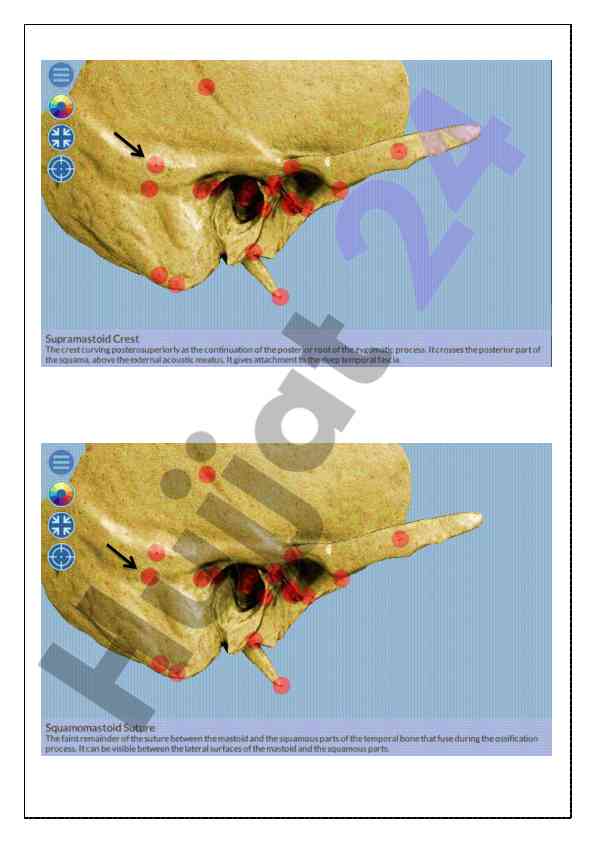

Kalla skeleti va chakka suyagi haqida umumiy ma'lumotlar taqdim etilgan o‘quv qo‘llanma. Anatomiyaga oid asosiy tushunchalar va strukturalar izohlangan.